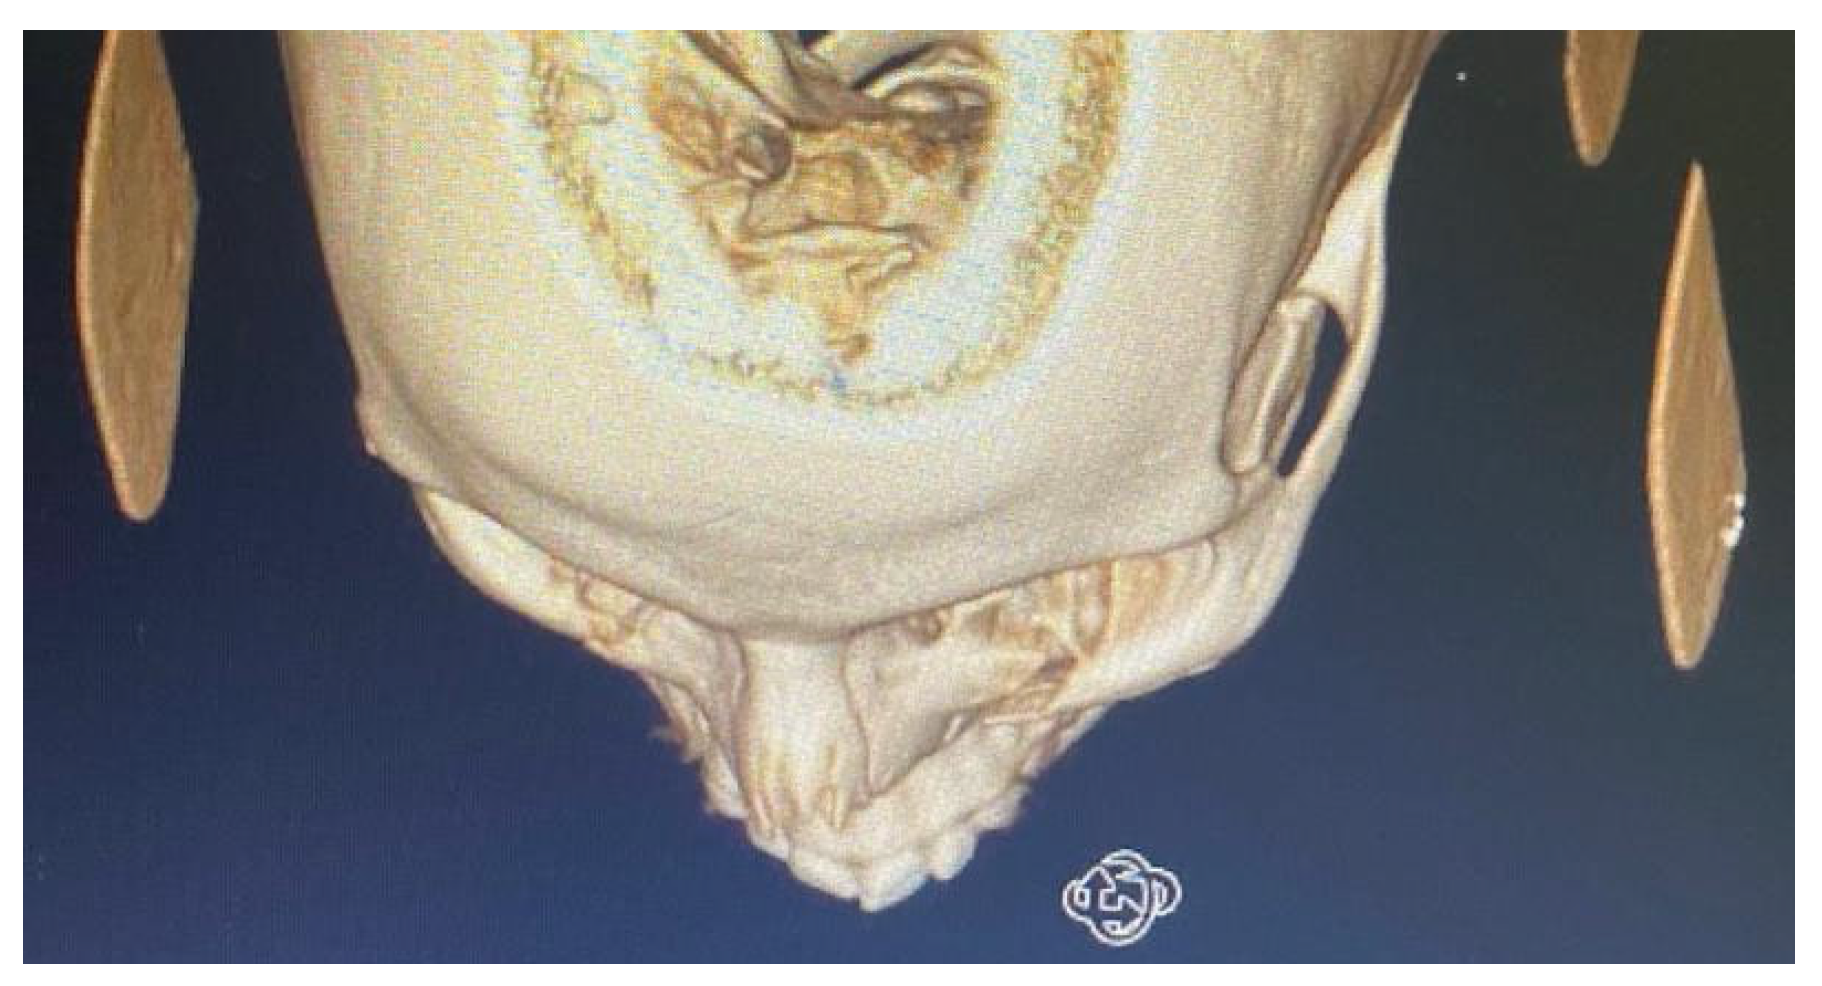

By counting the occurrence of the sites of fracture, either alone or combined, we found that the orbital floor (n = 52, 41.9%; Figure 1) and lateral wall (n = 31, 25.0%) were the most prevalent sites of bone fracture among the study patients (Figure 2, Figure 3 and Figure 4). Figure 5 illustrates the distribution of the causes of trauma.

Figure 4.

Orbital floor fracture with entrapment of the inferior rectus muscle; patients present with vertical gaze diplopia and restriction of upgaze.